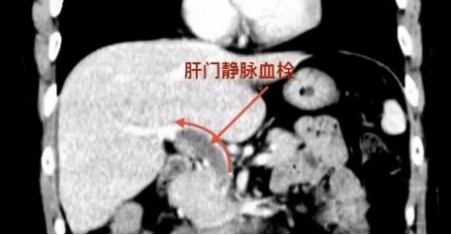

然而,由于服药后出现胃肠道不适,黄先生自行停药一周。不料几天后,他左侧腹部突然剧痛难忍。外院CT检查结果令人震惊:门静脉及肠系膜上静脉广泛血栓形成,伴多发肠管淤血水肿。

门静脉血栓、肠系膜上静脉血栓均属于非常危急且凶险的静脉血栓疾病,如同一场发生在腹内的“血管瘫痪”:血栓造成静脉堵塞,引起门静脉系统压力增高,出现进行性加重的腹痛,伴发热、脾肿大、腹水增加等门静脉系统淤血的表现。最危险的并发症即为肠淤血坏死,肠系膜上静脉血栓的死亡率高达20%–30%。

术中,蒋小峰教授团队在超声引导下精准经皮穿刺肝内门静脉,切口仅如针眼大小,顺利建立操作通道。血管外科团队与肝胆外科团队配合密切,谨慎而迅速地将吸栓导管送至闭塞血管远端,对门静脉及肠系膜上静脉进行有序吸栓。术中血流迅速恢复,避免肠淤血坏死,手术时间短、创伤小。术后造影显示:门静脉血流恢复通畅,手术圆满成功。